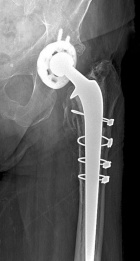

A.M. - 87 year old female with an asymptomatic posterior thigh soft tissue mass present for many years, the patient reports that it has increased in size over the past three months